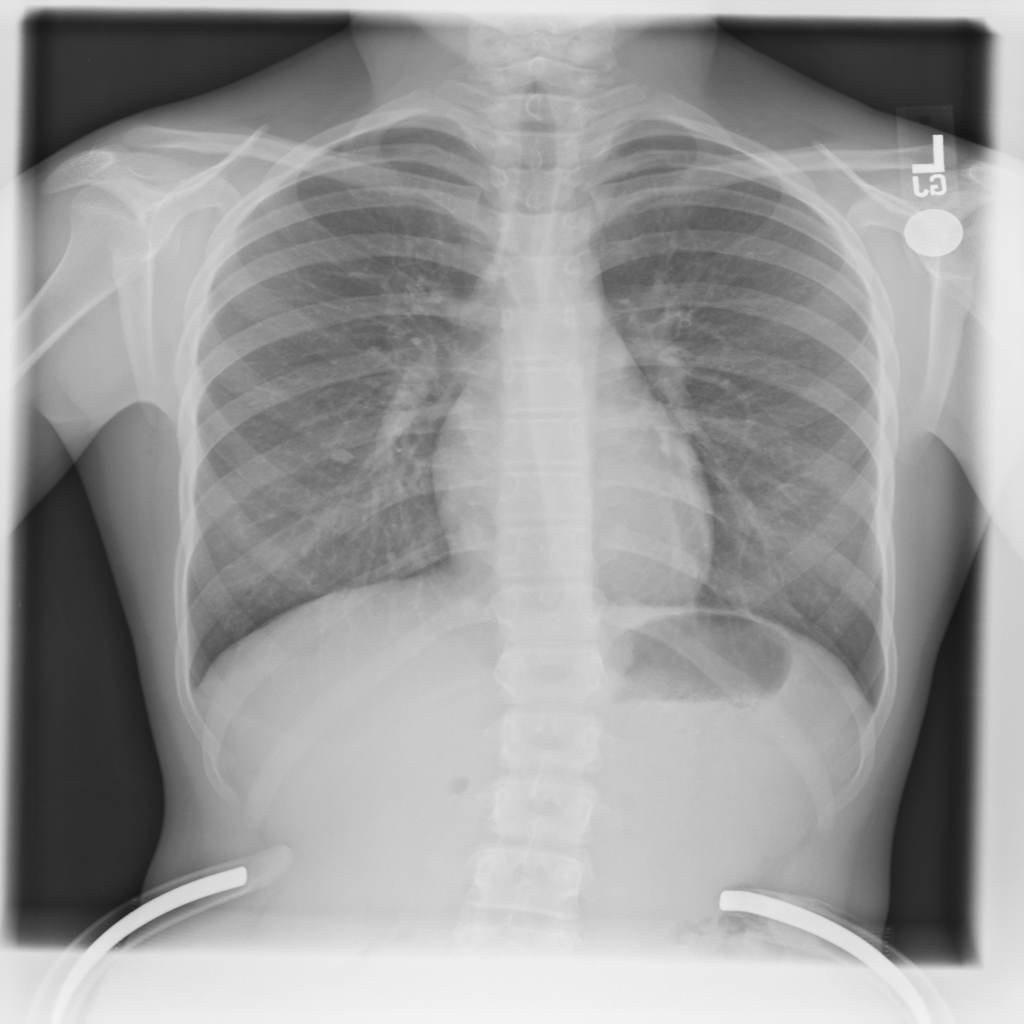

PAT-85BE · IMG-000Consolidation

PAT-85BE · IMG-000

AP